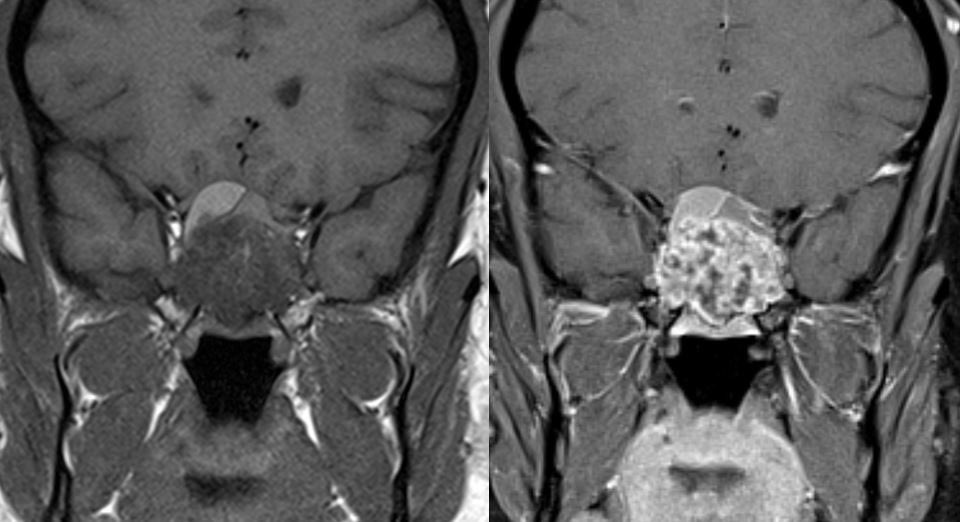

11 yo male with history of growth retardation and myopia presents with bradycardia and loss of consciousness.